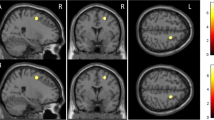

ROIs were generated by positioning the center of a 6-mm diameter sphere around coordinates defined a priori showing significantly higher activation in mixed-sex groups of young versus elderly adults (Young–Elderly contrast) as well as in mixed-sex groups of elderly adults versus patients with AD (Elderly–AD contrast) [8]. Due to demonstrated involvement in functional brain aging and AD, we explored a total of four ROIs, all of them in frontal or hippocampal cortices. We included three ROIs from the Young–Elderly contrast coordinates, consisting of two left inferior frontal gyrus ROIs (centered upon the following coordinates: X=−45, Y=47, Z=3; X=−42, Y=13, Z=24), and one ROI in the right hippocampus (centered upon the following coordinates: X=30, Y=−24, Z=−11). A second ROI in the right hippocampus was included from the Elderly–AD contrast (centered upon the following coordinates: X=15, Y=−24, Z=−16). Hippocampal ROIs (Young–Elderly and Elderly–AD) were located in the right medial and lateral regions of the posterior/mid hippocampus [39]. The ROI centered upon coordinates from the Young–Elderly contrast was more lateral/proximal than the ROI centered upon coordinates from the Elderly–AD contrast (Fig. 1).

Locations of spherical regions-of-interest from coordinates from Sperling and colleagues [8] are shown in Montreal Neurological Institute (MNI) space

We next asked: Is the functional response to encoding of novel face-name pairs in predetermined ROIs different between BSO, AMC, and SM? To determine this, we extracted task-related parameter estimates for Novel–Repeat face-name encoding in some of the same regions in which Sperling and colleagues previously reported less activation for a mixed-sex group of AD patients compared to cognitively healthy elderly adults (Elderly-AD contrast) and less activation for a group of elderly compared to young adults (Young–Elderly contrast), including ROIs in the right posterior medial and lateral hippocampus and left inferior frontal gyrus [8] (ROIs highlighted in Fig. 1).